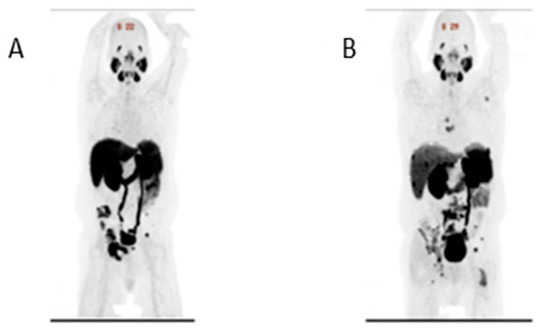

2. Case Report